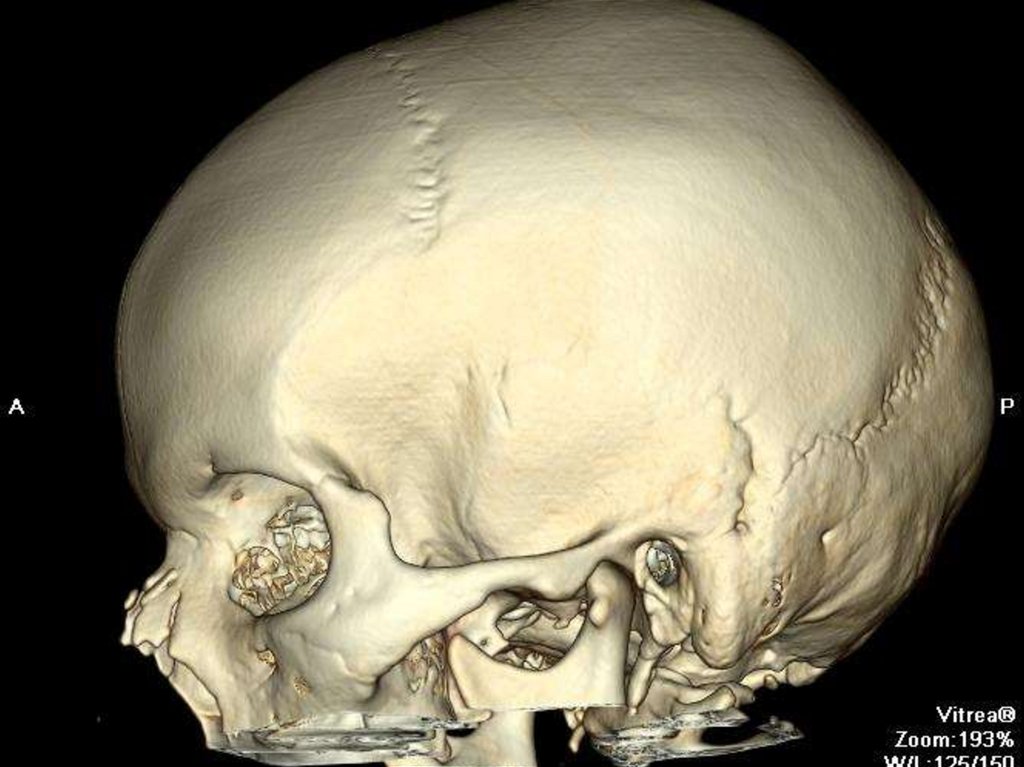

152. Стеноз наружного слухового прохода

Пороки развития

Стеноз наружного слухового

прохода